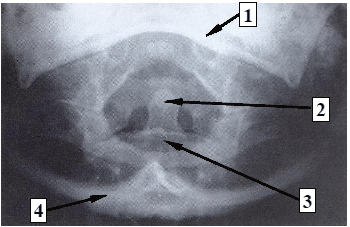

Assinale a alternativa que corresponde à sequência numérica (1, 2, 3 e 4) correta das estruturas especificadas na imagem.

A

1. forame magno; 2. processo espinhoso; 3. espaço articular zigapofisário; 4. osso occipital.

B

1. osso frontal; 2. processo clinoide anterior; 3. corpo de C4; 4. arco zigomático.

C

1. mandíbula; 2. dente do áxis (C2); 3. corpo do áxis (C2); 4. osso occipital.

D

1. osso occipital; 2. processo espinhoso; 3. clivo; 4. osso parietal.